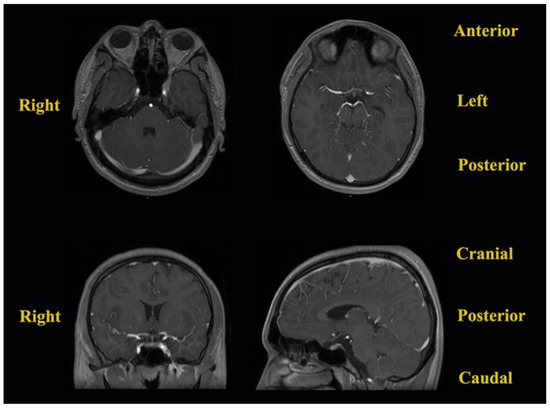

Given the amount of time that had passed since the initial discovery of the intracranial lesion (3 months), contrast-enhanced MRI was repeated (Figure 3). The results showed a small lesional growth, and the new dimensions described were 30.7/34/24 mm (transversal/craniocaudal/anteroposterior). The mass lesion had an inhomogeneous structure due to the presence of a solid component with moderate enhancement, a hemorrhagic component, and a liquid component with high levels of protein. The hypophyseal gland was declivitous and flattened from the superior view, while the optic chiasm was slightly pushed from the posterior and superior views.

Figure 3. Preoperative contrast-enhanced brain MRI: (A) axial T1 contrast-enhanced Fast Spoiled Gradient-Echo (FSPGR) sequence; (B) sagittal contrast-enhanced T1-weighted multiplanar reformation/reconstruction (MPR) sequence; (C) coronal contrast-enhanced T1-weighted MPR sequence; (D) coronal T2-weighted FSE sequence; (E) axial T2-weighted FLAIR FS sequence.

Following this investigation, a brain CT scan was performed to obtain more imagistic details (Figure 4).

The results depicted a tumoral mass, well delimited and localized at the median line in the suprasellar cistern and without a surrounding edema, without contrast enhancement, and with intrasellar prolabation. The lesion had a slightly inhomogeneous structure given the presence of areas with high densities (−27 UH, compared to −116 UH), corresponding to microcalcifications/hemorrhages/saponification of fats.

Subsequent cerebral angiography excluded any intracranial vascular malformations and highlighted the relationships with the neighboring blood vessels. An intracranial non-enhancing compressive mass lesion was determined, with a bilateral A1 segment of the anterior cerebral artery’s ascension (a positive “vault sign”).

After these investigations, the differential diagnoses comprised first and foremost an intracranial dermoid cyst given the hyperintense aspect in the T1-weighted sequence and the variable aspect in the T2-weighted sequence on MRI, as well as the well-defined low-attenuation and non-contrast-enhanced aspect in the CT scan [12]. The second option was craniopharyngioma given the hyperintense aspect in the T1-weighted sequence, with vivid enhancement, and the variable aspect in the T2-weighted sequence on MRI [13]. However, the CT scan aspect was not necessarily compatible with this type of lesion [13]. The third option was represented by a PitNET with intratumoral apoplexy given the moderate enhancement in the T1-weighted sequence and the variable aspect in the T2-weighted sequence on MRI [14]. However, the CT scan images were incompatible with this suspected lesion. The fourth option was a teratoma due to the hyperintense aspect and protein-rich fluid’s moderate enhancement in the T1-weighted sequence and the variable aspect in the T2-weighted sequence [15]. Nevertheless, the CT scan images did not suggest this type of lesion.